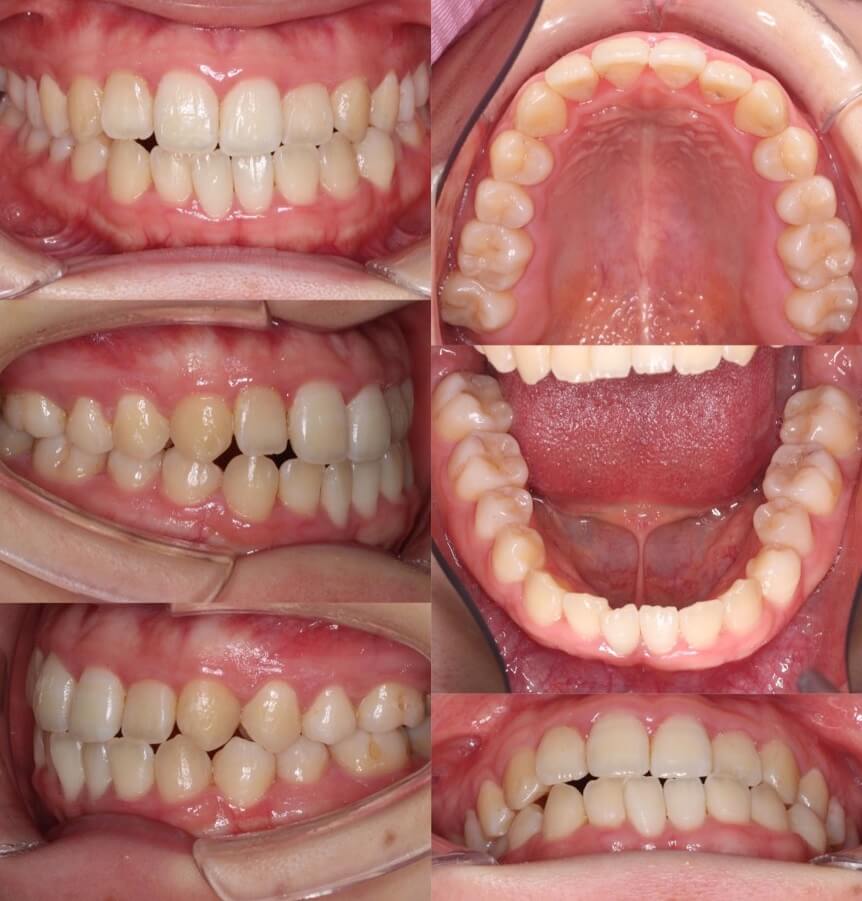

大学生女性・唇側矯正装置・小臼歯4本抜歯

<顔のビフォーアフター>

<症例概要>

主訴:受け口・前歯のガタガタ

年齢・性別:大学生女性

住まい:千葉県八千代市

症状:反対咬合・重度叢生・開咬

治療方針:上下小臼歯抜歯・空隙閉鎖

治療装置:唇側矯正装置

固定装置:上バイヘリックス装置・III級顎間ゴム

抜歯:上第二小臼歯・下第一小臼歯・下親知らず(計6本)

治療期間:2年2か月

リテーナー:上下フィックスタイプ+クリアタイプ

治療費用:968,000(税込)

代表的副作用:痛み・治療後の後戻り・歯根吸収・歯髄壊死・歯肉退縮

歯が並ぶスペース不足が大きく、前歯の不揃いが強いケースです。また、上下の前歯は開咬状態になっており咀嚼障害もあります。上下小臼歯抜歯を行いできたスペースをうまく利用して前歯を並べ、III級顎間ゴムを使用し下の歯列全体を親知らずを抜歯した後方へ起こしました。非常に難しい治療方針でしたが、ご本人がゴムの使用を頑張ってくれたので予定より早く治療期間も終わり、審美的にも機能的にも良い歯並びになりました。